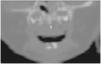

Durante el segundo ingreso se le realizó una TC de las fosas nasales en la que se observó la disminución de la distancia entre ambos procesos nasales del maxilar (fig. 1), incisivo central único congénito (fig. 2a y b) y paladar triangular (fig. 3) con cresta central (fig. 4), hallazgos compatibles con ECOP.

La paciente que aquí se presenta cumplía con estos hallazgos descritos. Asimismo, presentaba una pequeña cresta ósea en la línea media por debajo del paladar duro en la reconstrucción coronal (fig. 4) y un gran diente incisivo único central (fig. 2). Éstas son alteraciones típicamente asociadas a la ECOP; es particularmente destacable la alteración de la dentición, ya que el megaincisivo central único puede ser una manifestación de la holoprosencefalia, por lo que se indica un estudio de imagen cerebral, preferiblemente una resonancia magnética (RM)1,4,6. En el presente caso se realizó ecografía y RM cerebral, que no mostraron alteraciones.